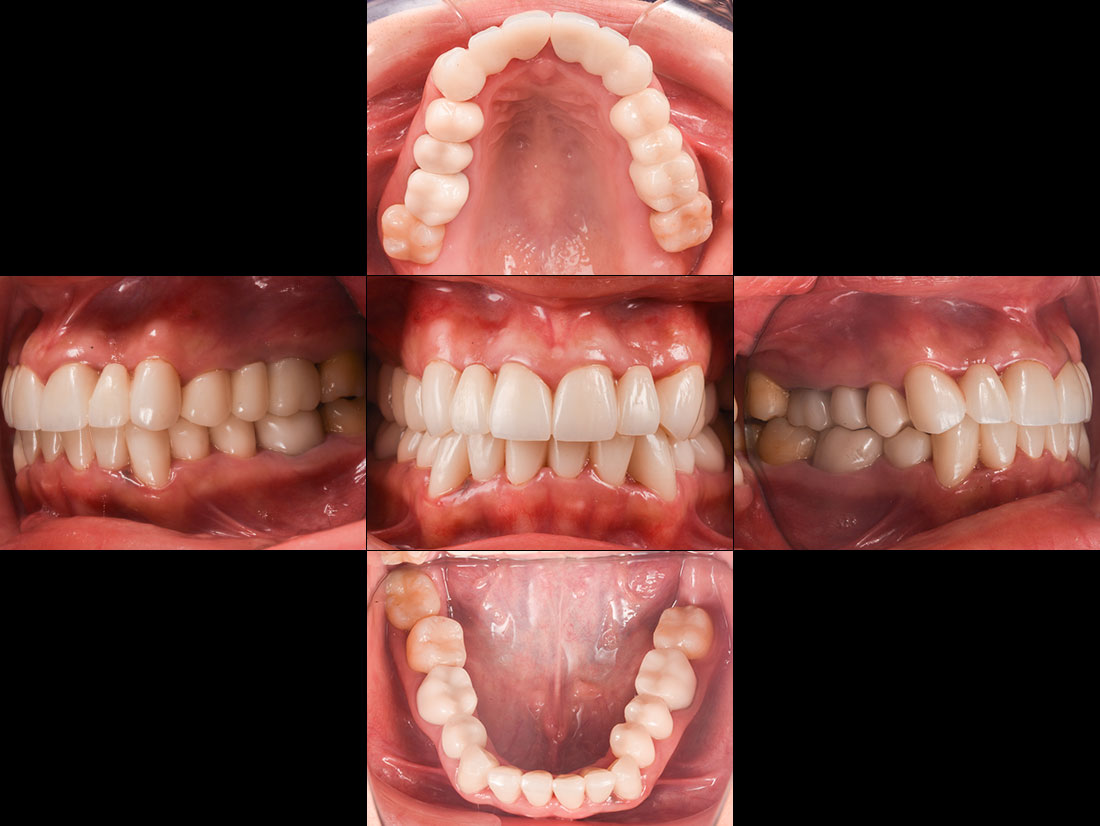

治療症例 Case1

Treatment cases

ご相談内容

- 歯並びが気になる

- 矯正をする時間が取れないので被せ物で治していきたい

治療前

治療後

今回は前歯をグラデーションカラーのジルコニア、奥歯をセレックで治療しました。

見た目の美しさのポイントになるスマイルラインも整っています。